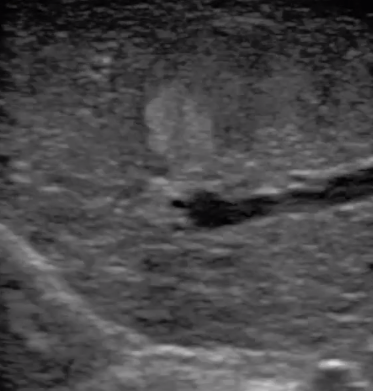

胎移植臨床圖